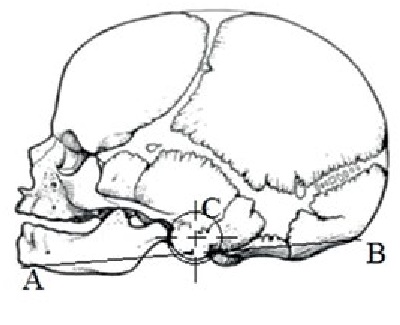

Results. During the mid-gestation period, with the growth of the fetus, the auricle normally shifts upward relative to the mandible. At the beginning of the study period, the auricle is located just below the angle of the lower jaw. Its central part (C) is below the line (AB) connecting the gnathion point and the external occipital protuberance. The perpendicular from the conditional center of the auricle to the line AB is half the diameter of the auricle 3.7 ± 1.1 mm. In the second age group, the auricle is located at the level of the branch and angle of the lower jaw Its conditional center (C) is below the line AB and is ¼ of the diameter of the auricle 3.1 ± 0.8 mm. By the end of the mid-gestation period, the auricle is displaced to the level of the processes of the lower jaw above the notch. Its central part is above line AB, the perpendicular from point C to line AB is 6.1 ± 1.4 mm.

В работе определяли топографо-анатомические взаимоотношения нижней челюсти и уха плода, расположение в разные возрастные периоды центральной части (точка С) ушной раковины относительно нижней челюсти (АВ – линия, соединяющая точку гнатион и наружный затылочный выступ). Ушная раковина рассматривалась как фигура, приближенная к окружности. Внутри окружности были проведены две перпендикулярные линии, точка пересечения которых являлась центром симметрии геометрической фигуры и использовалась в качестве условного центра ушной раковины (обозначенного на рисунках как точка С).

Ушная раковина в течение промежуточного плодного периода при росте плода в норме смещается вверх относительно нижней челюсти. В начале изучаемого периода ушная раковина расположена чуть ниже угла нижней челюсти. Ее центральная часть (С) находится ниже линии (АВ), соединяющей точку гнатион и наружный затылочный выступ. Перпендикуляр от условного центра ушной раковины до линии АВ составляет половина диаметра ушной раковины и в среднем равен 3,7±1,1 мм (таблица 1).

Возрастной период | Схема изменений топографических взаимоотношений ушной раковины плодов относительно нижней челюсти | Ультразвуковая сканограмма головы плода |

14–18 недель | Возраст 14 недель, пол мужской | |

Примечание. 1 – наружный затылочный выступ; 2 – гнатион; 3 – ушная раковина.